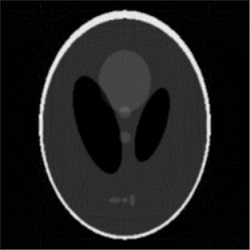

Given the problems we have pointed out regarding the first randomized algorithm, we have focused on the results obtained by the second randomized algorithm. For the parameters that we have fixed above, the results obtained by running the second randomized algorithm with 125000 iterations are given in Fig. 4 and Fig. 5 (Fig. 4 (a) is Fig. 2, and Fig. 5 (a) is Fig. 3). In both cases, the correction is significant, and the result of correction is very close in terms of reconstruction quality to the result obtained by running each of the two analytical algorithms alone with full view of 360 projection angles. That is, the result shown in Fig. 4 (b) is comparable to the result shown in Fig. 6, and the result shown in Fig. 5 (b) is comparable to the result shown in Fig. 7, which means a reduction in the number of views of (in Figs. 6 and 7 the reconstruction is more homogeneous, but with more visible artifacts). From the experiments we have conducted, we have remarked that the number of views can be reduced up to about and the results are still comparable to the results obtained by the analytical algorithms with full view, provided an appropriate number of iterations is chosen.